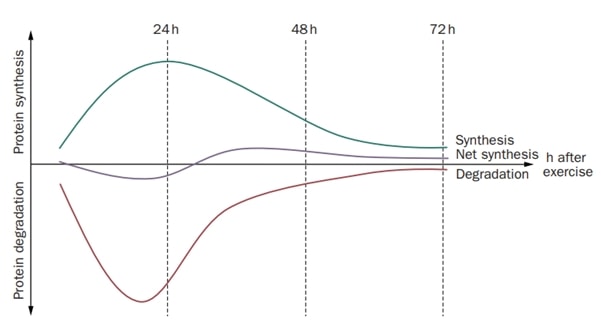

5. Интензивното натоварване на сухожилията води до нетна деградация на колагена за период до 36 часа. Проучване на Magnussen et al.(2010) показва този ефект при три групи много интензивни упражнения, които са 36 км бягане, 1 час повтарящо се ритане и 10 серии от 10 повторения на колянно разгъване при 70% максимална доброволна контракция. Това означава, че се нуждаем от достатъчно време за възстановяване, за да предотвратим тендинопатията, и че е препоръчително тренировките за сухожилията да се провеждат на всеки втори ден или по-рядко.